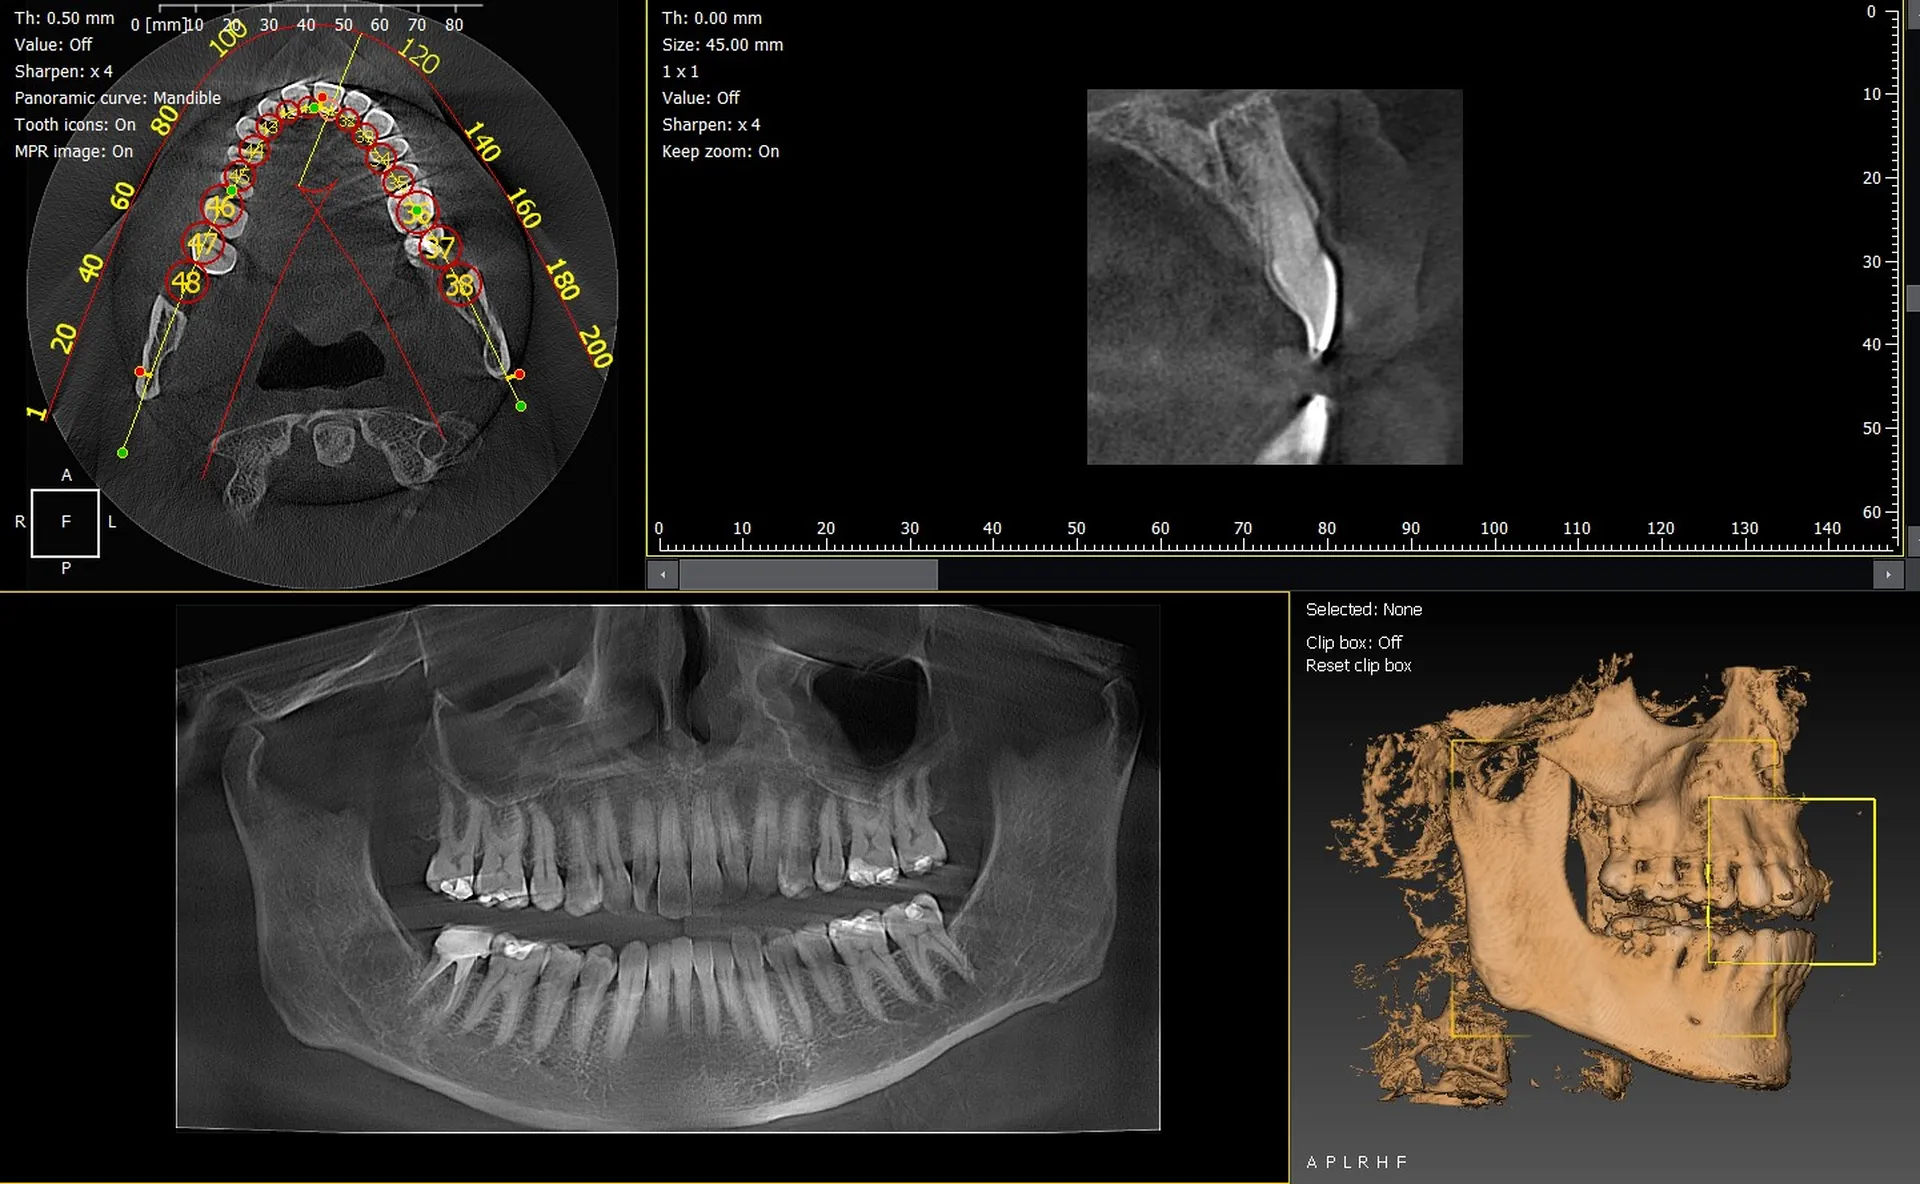

Les cabinets dentaires de Hyères et du Var (83) se modernisent grâce à l’installation de panoramiques CBCT 3D performants, tels que le VistaVox de Dürr Dental et l’Owandy I-Max 3D. Ces équipements offrent une imagerie de haute précision indispensable pour l’implantologie, l’endodontie et le diagnostic avancé.

VistaVox 3D : précision et volume optimisé 130x85

Le VistaVox se distingue par :

• un volume adapté à l’arcade dentaire,

• une très haute résolution pour diagnostics complexes,

• une réduction de dose performante,

• un positionnement rapide et ergonomique.